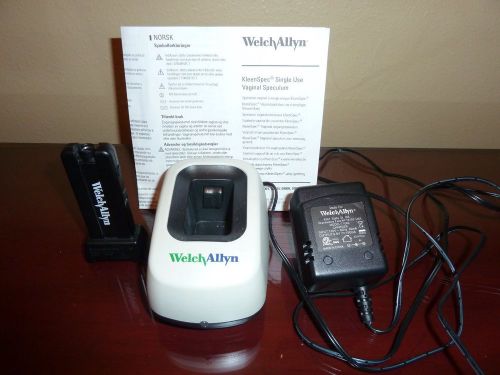

Welch Allyn KleenSpec Vaginal Specula Cordless Illuminating System & ChargeBase

Welch allyn kleenspec vaginal illuminator system, complete 78810

Welch Allyn Kleenspec 790 Series Illuminator Vaginal Specula Item# 79900 New

WelchAllyn Vaginal Specula Illumination System 78810